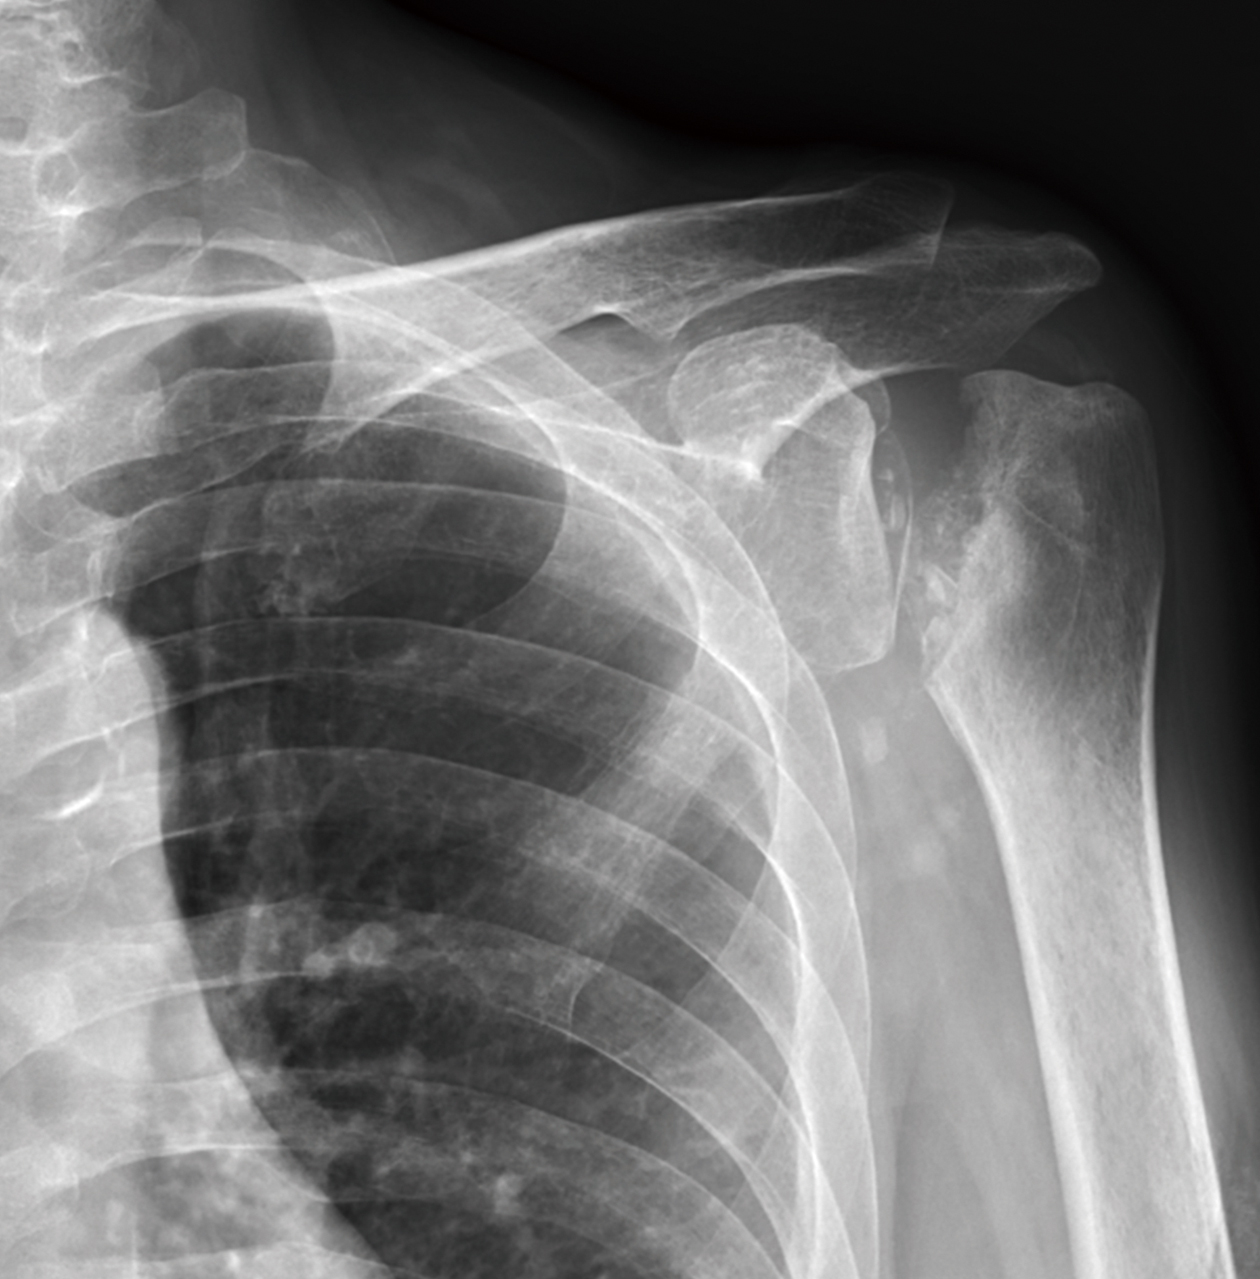

黃先生52歲,左肩疼痛多年,手無法上舉,一年來症狀加劇,經檢查發現肱骨頭缺血性壞死併肩關節炎,核磁共振發現大片全層旋轉肌破裂,接受了反置式人工全肩關節置換手術治療,並投入計劃性復健治療,目前疼痛消失,手已可上舉接近150度。

左側肱骨頭缺血性壞死續發關節炎併旋轉肌腱斷裂,經反置式人工全肩關節置換手術治療。